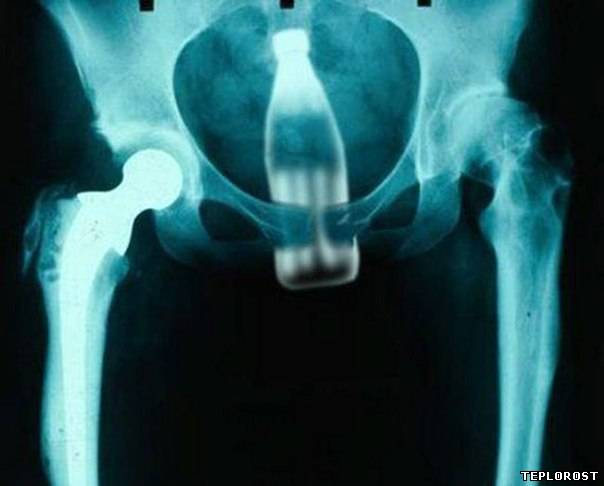

Стеклянная бутылка в заднем проходе у женщины.

Бутылка Coca-Cola, застрявшая в «детородном» органе